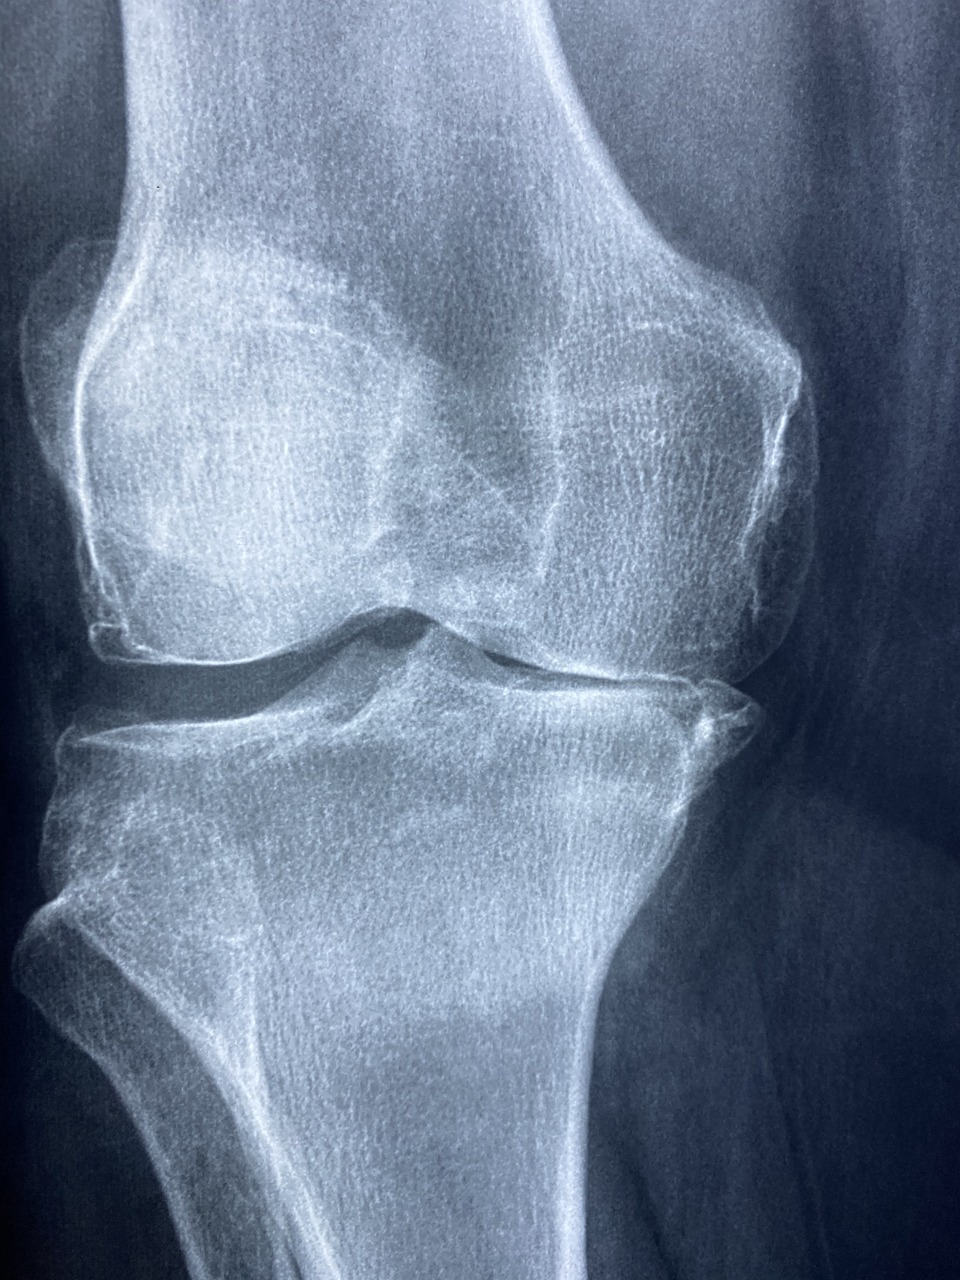

1. 연골 보호 & 관절 건강 개선

✔ 콘드로이친은 연골의 수분을 유지하고 탄력을 높여 관절을 보호하는 역할을 합니다.

✔ 퇴행성 관절염(골관절염) 환자의 통증을 완화하는 효과가 있습니다.

✔ 무릎 관절뿐만 아니라 손목, 어깨, 허리 관절 건강에도 도움을 줍니다.

3. 뼈 건강 & 골다공증 예방

✔ 콘드로이친은 뼈 조직의 건강을 유지하고, 칼슘 흡수를 촉진하여 골다공증 예방에 도움을 줍니다.

✔ 나이가 들면서 뼈 밀도가 감소하는 것을 방지하는 효과가 있습니다.